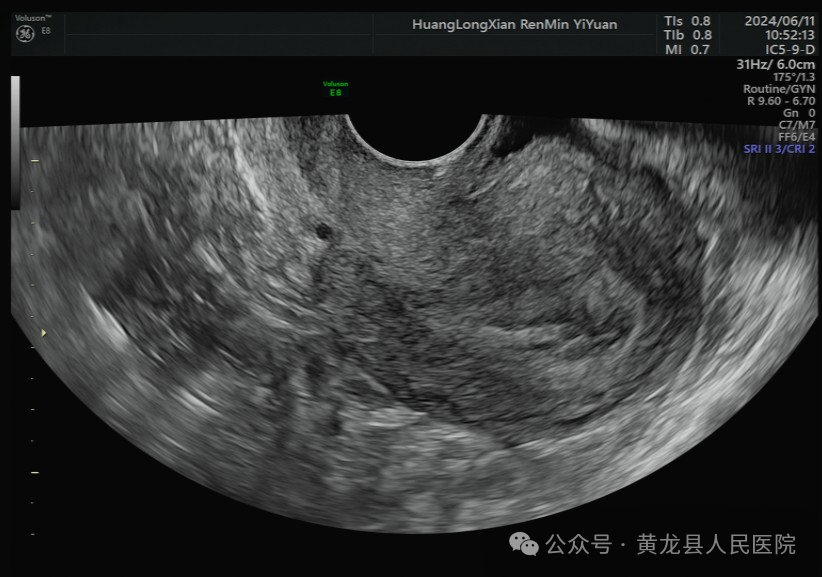

据统计,子宫内膜息肉在妇女子宫异常出血情况的诊断中占比:绝经前10-40%,绝经后10.1-38%,这些数据显示,子宫内膜息肉是女性子宫异常出血中的一个重要因素,尤其在绝经前后的女性中最为常见。随着医疗技术的不断提高和超声医疗设备的更新,图像清晰度不断提升,使超声在各个器官的诊断有了突飞的进步,特别是阴道超声的应用,对子宫内膜息肉的诊断也变得更加准确。

我院超声科于2019年引进美国GE Voluson E8四维彩超诊断仪,该设备是国内外彩超领域的佼佼者,是兼具优异图像和快捷工作效率的超声系统,为获取优异图像提供了技术保证,设备在产前筛查、胎儿心脏、生殖、妇科盆底超声、围产超声等领域均处于世界先进水平,可进行各类妇产科疾病成像,为女性健康保驾护航。其腔内探头是子宫内膜息肉检出率的主要功臣。